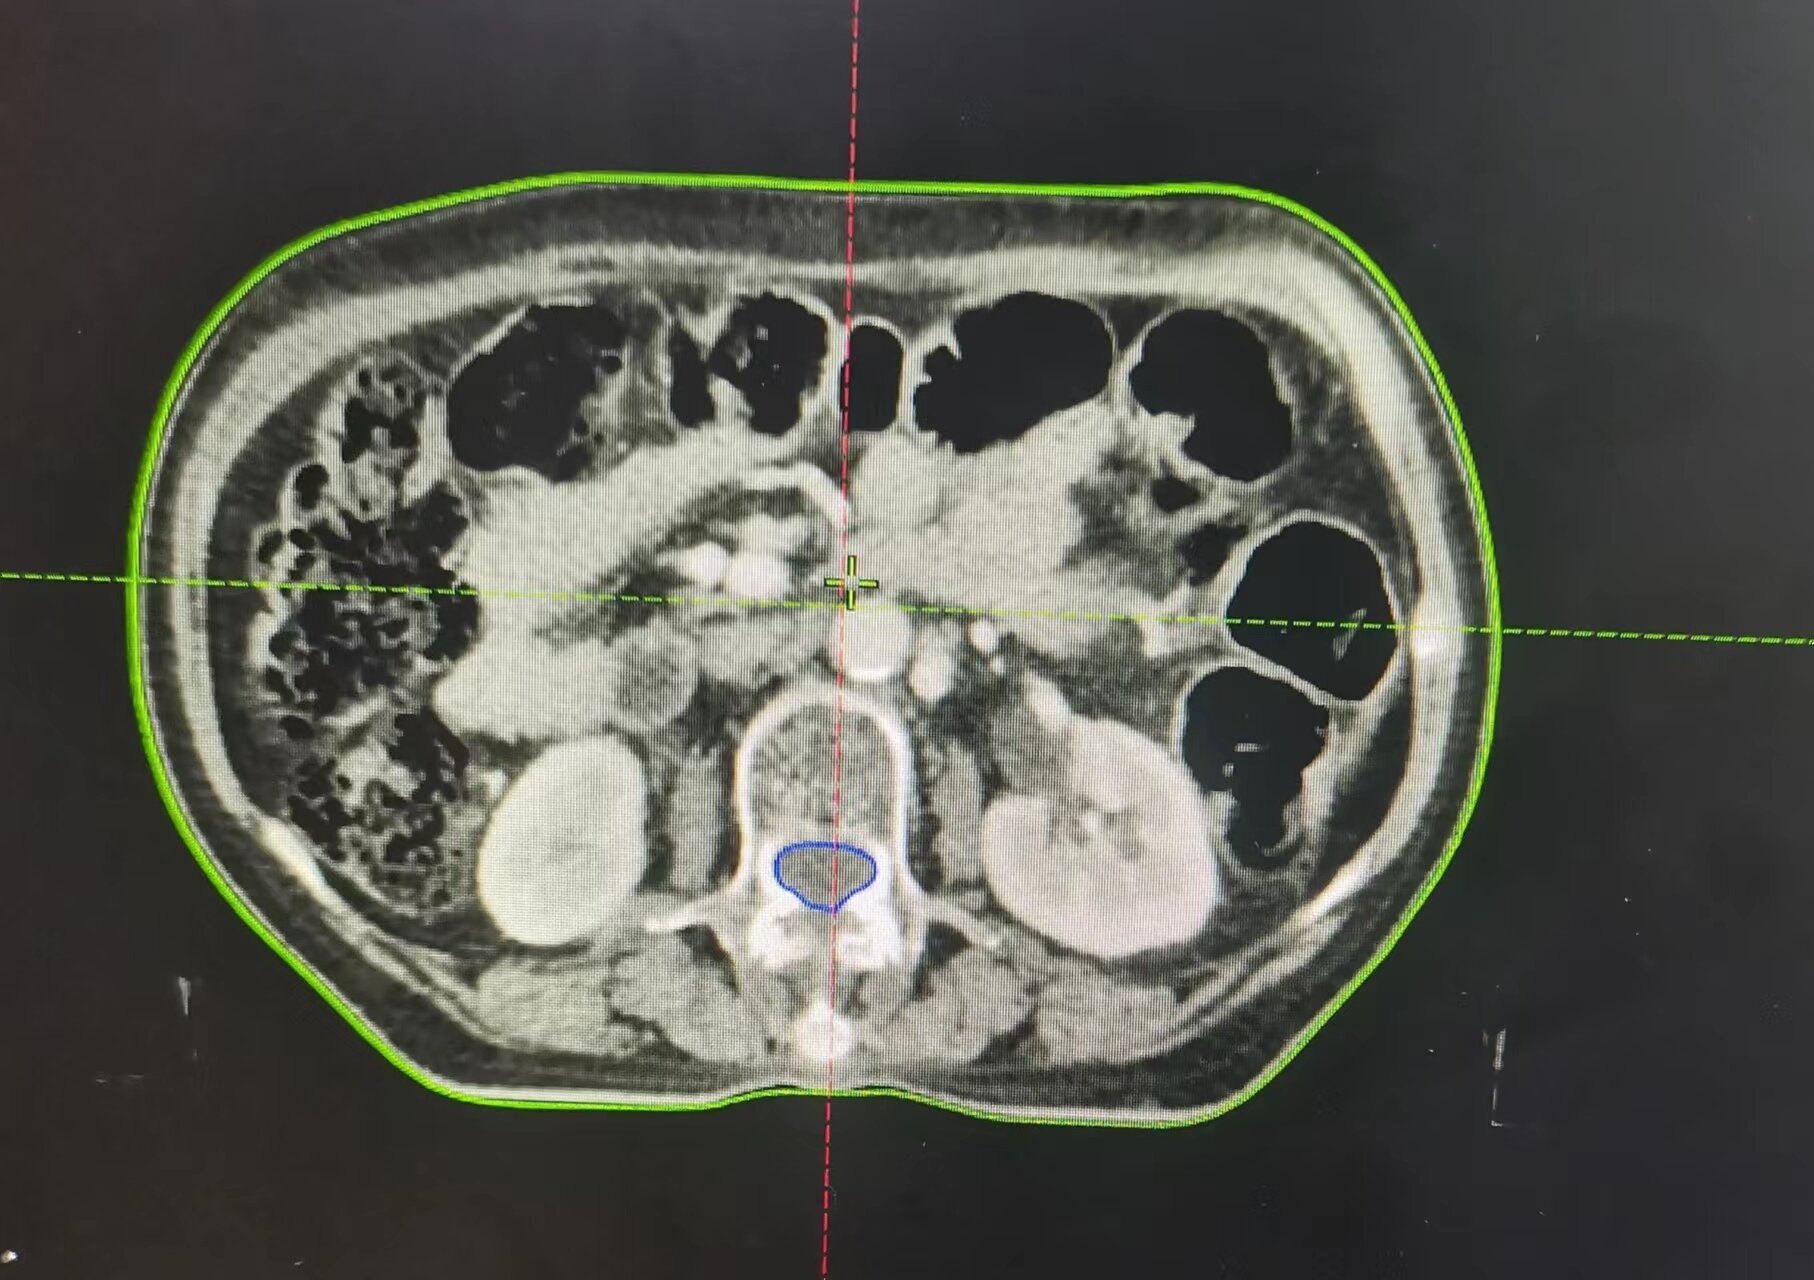

近日,75歲的宮頸癌晚期患者朱阿姨,接受市二院放療科的16次精準(zhǔn)放療后,復(fù)查CT顯示:腹膜后及盆腔轉(zhuǎn)移淋巴結(jié)消失,宮頸腫瘤較前明顯縮小。

因老人出血量較大,趙亮接診后立即給予止血治療,出血暫時控制住了,但是腫瘤消不掉,出血現(xiàn)象還是會反復(fù),甚至可能出現(xiàn)危及生命的大出血。考慮到患者病期晚、年齡大、合并基礎(chǔ)疾病多,趙亮帶領(lǐng)科室團(tuán)隊經(jīng)過仔細(xì)討論及評估病情后,決定盡快進(jìn)行三維精準(zhǔn)放射治療及同步化療,同時給予止血及對癥支持治療。

開始朱阿姨非常沮喪,一度想放棄治療,趙亮耐心地跟她溝通,用科室治療成功的案例來鼓勵她。經(jīng)過5天的治療,患者局部出血大大改善,治療過程中也沒有感到不適,放療11次后患者陰道出血狀況完全緩解,腹部疼痛較前明顯改善。朱阿姨非常高興,逢人便說,放射治療解決了她的問題。家屬看到朱阿姨的變化,連連驚嘆:“真是沒有想到有這么好的治療效果,開始我們還擔(dān)心放療的副作用,沒想到現(xiàn)在技術(shù)這么好,副作用這么小,現(xiàn)在什么不舒服都沒了。”目前,患者正在非常積極的繼續(xù)配合后續(xù)相關(guān)治療。